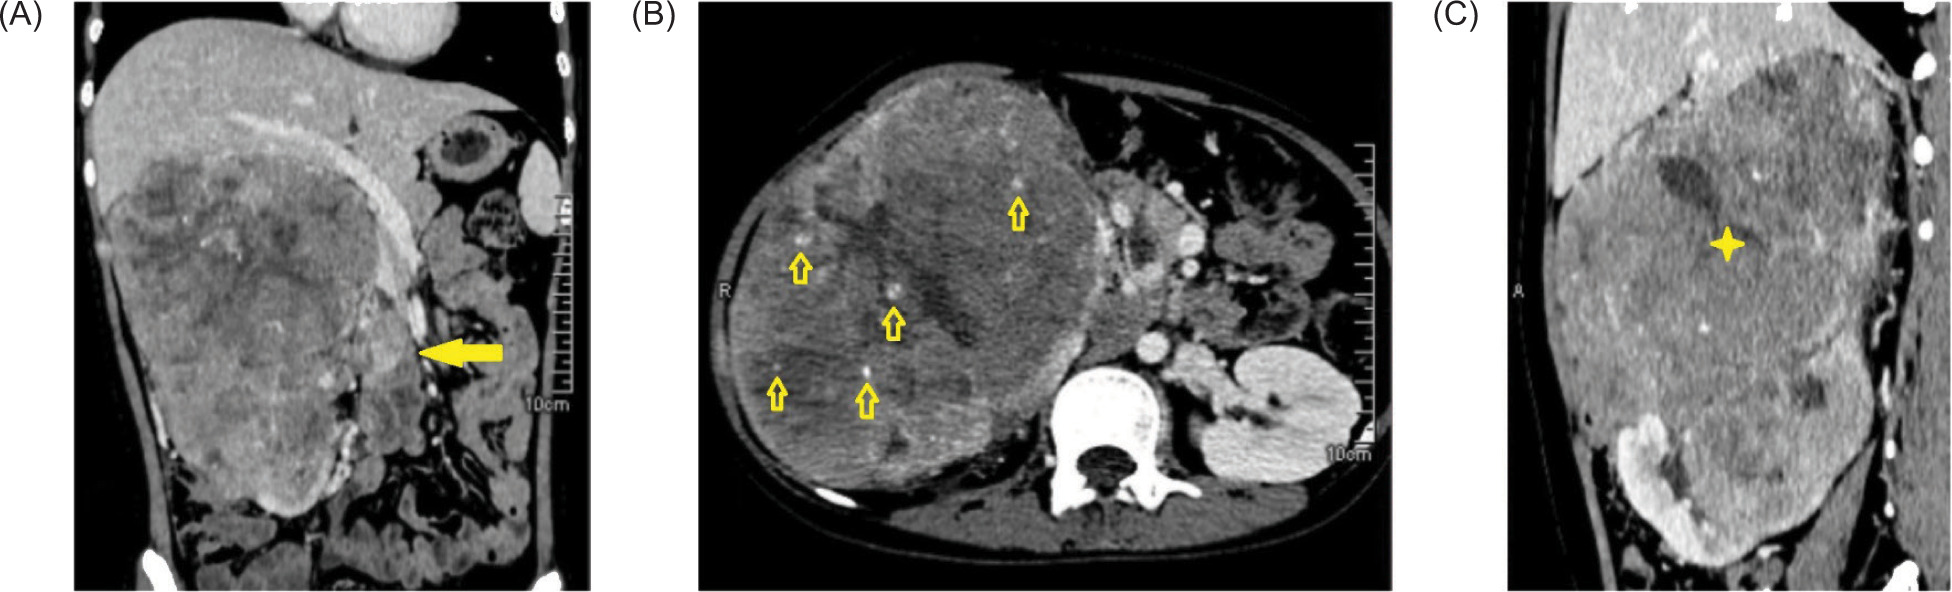

A 19-year-old female presented with a clinical history of dysuria and a progressively enlarging, eventually palpable right flank mass. A computed tomography (CT) scan of the abdomen (Figure 1) revealed a large, lobulated, heterogeneously-enhancing renal mass (Figure 1C) with internal calcifications (Figure 1B) and hypodense necrotic areas. Thrombosis of the right renal vein and inferior vena cava were also detected (Figure 1A).

Figure 1: Contrast-enhanced CT-scan of the whole abdomen. (A) Renal mass with renal vein thrombosis (arrow). (B) Intratumoral calcifications (arrows). (C) Large heterogeneously-enhancing mass (star) arising from the kidney.